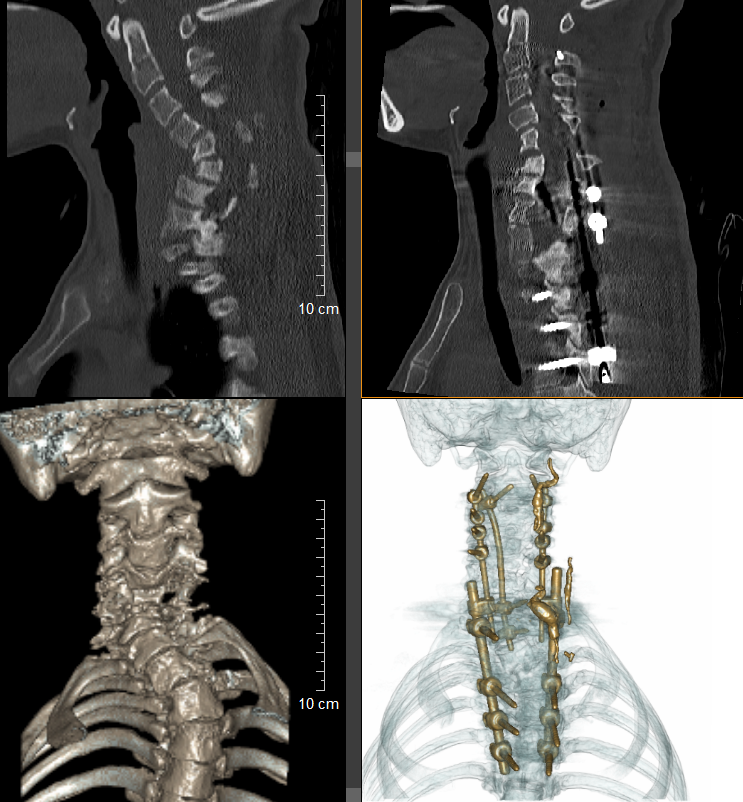

患者入院后,脊柱外科一科高度重视,组织了多学科协作(MDT)团队。由神经外科医生黄伟佳率先开展介入下椎动脉畸形栓塞术,成功栓塞了3条导致椎动脉畸形的关键血管,随后患者转回脊柱外科一科实施矫形手术。按照治疗计划,医生先为患者进行了为期两周的头环重力牵引,以改善畸形,评估脊髓和神经矫形的耐受程度,为手术创造有利条件。两周后,黄敏军与脊柱外科一科主任王亮合作,为患者制定详细手术方案,并择期进行单一颈后路矫形重建手术,手术过程十分顺利,历时约4小时,出血量不到 600毫升。手术有效保留了颈椎部分活动度,且颈椎后凸畸形矫形率达到 70%,由术前的70°减少至术后21°。

术前术后的脊柱对比